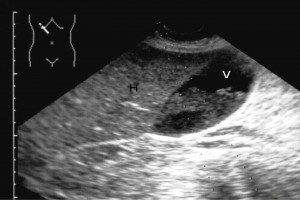

Diplomados en Ultrasonografía